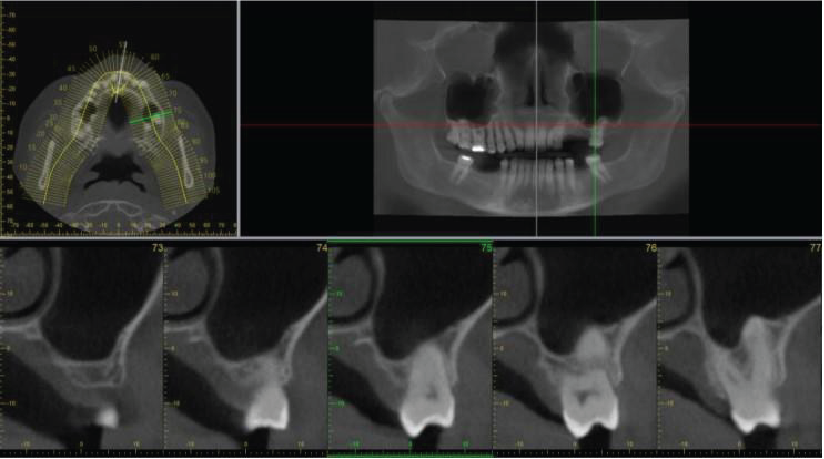

Image 1

Coronal cross-section through the maxillary antra and their ostia

There is coverage of all the nasal cavities and paranasal sinuses apart from the most superior parts of the frontal sinuses. There is deviation of the nasal septum to the right side, with a bony spur projecting into the right middle meatus. Asymmetries of the turbinate bones are associated with this, with relatively larger turbinates on the left side and with a paradoxical curvature of the left middle turbinate. No mucosal disease in the nasal cavities. The maxillary antra are aerated normally apart from very limited mucosal thickening at the medial part of the antral roof on the right side, close to the natural ostium. The ostia are patent bilaterally (image 1). Other paranasal sinuses are normally aerated. The deviation of the nasal bone anatomy has an effect on the width of the frontal recess (the drainage channel of the right frontal sinus leading into the ostio-meatal complex), but it is patent. Overall, the ostio-meatal complexes are patent bilaterally and the nasal cavity and paranasal sinus health is clear.